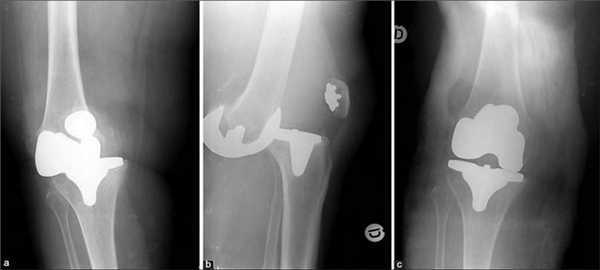

Как это выглядит после операции.

Одномыщелковая замена сустава на рентгене.